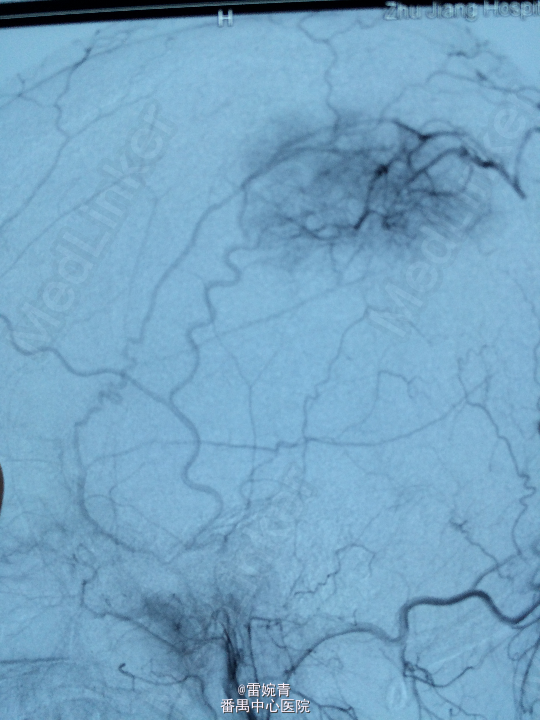

诊断:脑膜瘤 处理:先行DSA检查以明确脑膜瘤的供血动脉情况,见:肿瘤染色,肿瘤主要由左侧眼动脉供血,用Glubran胶将其闭塞,后择期行手术切除治疗。术后病理证实为脑膜瘤。